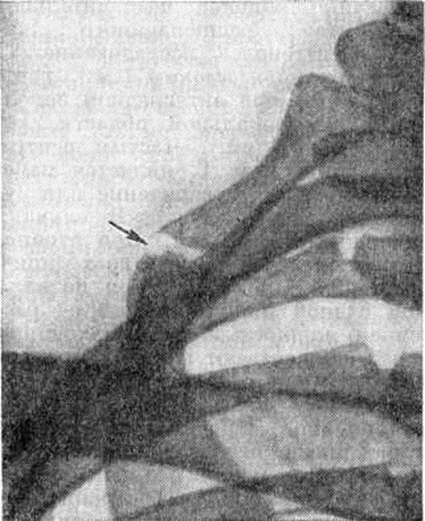

Клинические, картина характеризуется остро возникающей или постепенно нарастающей болью в области поражения. Через несколько часов (иногда дней) над пораженным ребром начинает формироваться равномерно плотная болезненная припухлость, постепенно занимающая все межреберье и возвышающаяся на 0,5—3,0 сантиметров над грудной стенкой. Боли усиливаются при движениях руками, подъеме тяжестей, чиханье, кашле, поворотах туловища, в положении лежа на больном боку. Нередко боли иррадиируют в шею, надплечье, руку, лопатку. Кожа над припухлостью обычной окраски, подвижная. Регионарные лимфатических, узлы не изменены, температура тела не повышается, какие-либо изменения в составе крови и мочи отсутствуют. Боли продолжаются от нескольких дней до нескольких недель и даже месяцев, припухлость исчезает значительно позднее. В редких случаях клинические проявления заболевания исчезают спонтанно в короткие сроки.

Диагноз в подавляющем большинстве случаев устанавливают на основании данных анамнеза и типичной симптоматики. Дифференциальную диагностику проводят с остеомиелитом (смотри полный свод знаний), специфическими формами перихондрита (смотри полный свод знаний) и остеохондрита (смотри полный свод знаний), костной мозолью после перелома (смотри полный свод знаний: Костная мозоль), доброкачественными и злокачественными опухолями и другие (смотри полный свод знаний: Грудная клетка).